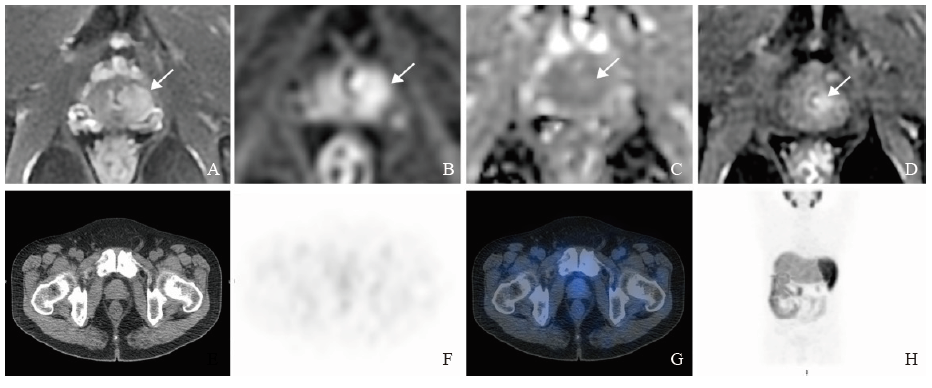

mpMRI combined with 99mTc-PSMA SPECT/CT to detect significant residual prostate cancer after neoadjuvant androgen deprivation treatment A 58-year-old patient received transuerthral resection of prostate and 3 months of neoadjuvant ADT with Gleason score 10, initial PSA was 8.23 ng/mL, PSA after neoadjuvant ADT was 0.685 ng/mL. Pathology after RP confirmed the presence of significant residual lesion. A: Foucal hyperintensity on T2WI of the left peripheral zone (arrow); B, C: The lesion showed hyperintensity on DWI and isointensity-mild hyperintensity on ADC image (arrow); D: Foucal mass-like early enhancement on DCE (arrow), PI-RR score 5; E: Cross-sectional view of the prostate on CT; F: Negative result on SPECT; G: Fusion image of SPECT and CT; H: Maximum intensity projection image."